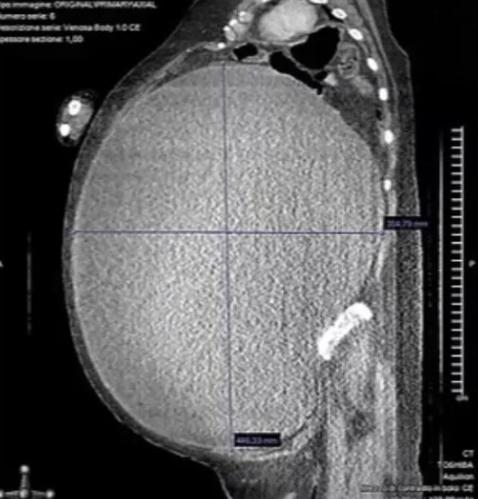

綜合報道,CT診斷發現,女子罹患邊緣性卵巢瘤(Borderline ovarian tumor,BOT),腹部完全被腫瘤佔據,醫生在進行子宮切除術前,排出了囊腫中37升的濃稠棕色液體,經過6個小時手術,才成功取出腫塊,女子期間失血6公升,手術後她住院留醫了2個月,一半時間都待在加護病房,還曾發生了心臟驟停。研究人員說,2年後,女子完全康復,沒有任何疾病。該病例報告近期發表在《美國病例報告雜誌》上。

CT診斷發現,女子罹患邊緣性卵巢瘤(Borderline ovarian tumor,BOT),腹部完全被腫瘤佔據。(網上圖片)